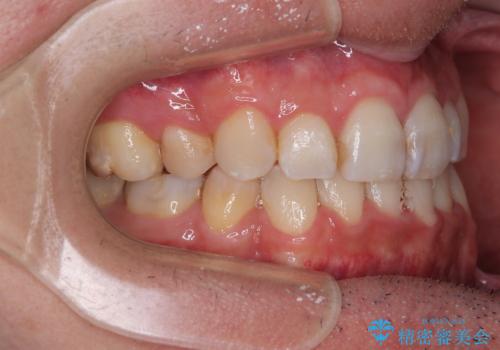

裏側装置での交叉咬合改善は非常に困難なもので、頻繁に装置の脱落がありました。

それでも想定以上に治療期間は長期化せず、咬み合わせも口元も満足のいく仕上がりとなりました。